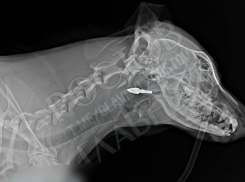

Общество В Ростове собаку со стрелой в голове доставили в ветклинику

Пес несколько дней побудет в больнице